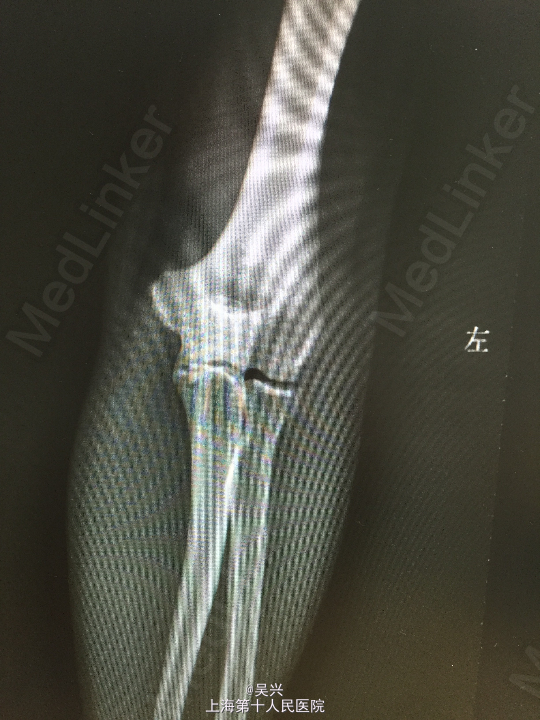

左肘外伤肿痛畸形3小时。左肘屈曲位着地受伤。

急症查体见肘关节肿胀、触痛,存在向后方半脱位及外侧松弛不稳定。

诊断:左肘恐怖三联症。 处理:术前准备,抗炎消肿治疗,术后三天行左肘正中切口显露尺骨冠状突,术中见尺骨冠状突粉碎性骨折,用两枚微型空心螺钉固定,发现屈肘位置仍有肘关节半脱位趋向。予伸肘位石膏固定,术后2周改屈肘45度位石膏固定,术后4周拆石膏,能逐渐屈肘至90度。

随访:术后1月患者肘关节稳定性良好,伸肘0度,屈肘90度,理疗辅助功能锻炼中。 讨论:肘关节脱位(半脱位)伴尺骨冠状突骨折、桡骨小头骨折称为肘关节恐怖三联症。该症存在极度肘关节不稳定,容易发生向后方、侧方脱位。一般单纯尺骨冠状突骨折极少,多伴有桡侧结构损伤和关节不稳定。肘关节恐怖三联症治疗原则一般是复位固定尺骨冠状突和桡骨小头,修复桡侧副韧带。我们术中发现固定尺骨冠状突后关节仍然不稳定,但桡骨小头因不全骨折需要石膏固定,因此不采取手术修复外侧副韧带,而是石膏固定,术后也取得较好的效果。